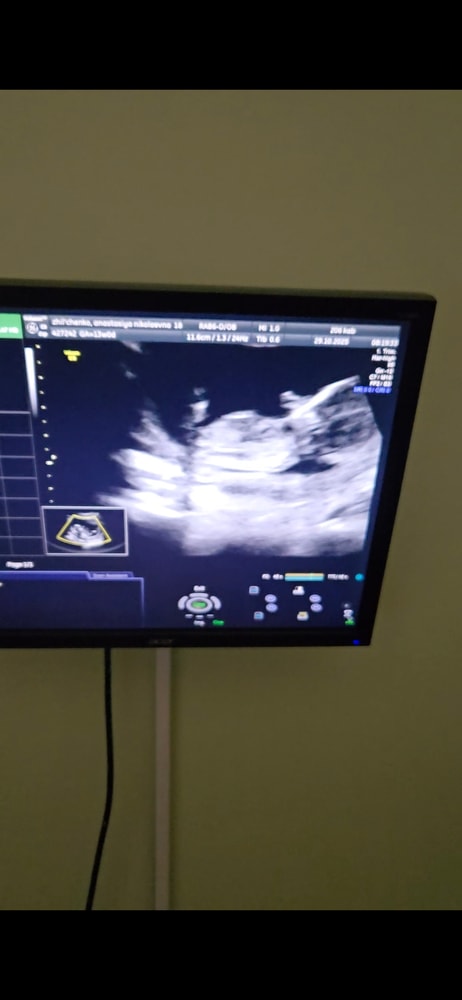

Мальчик/девочка?

Анализы, скринингиХотелось бы послушать знатоков по половым бугоркам 😄 если видно, подскажите) с видео сделала фото

Не понятно - то ли ножка, то ли бугорок. Пока похоже на мальчика.